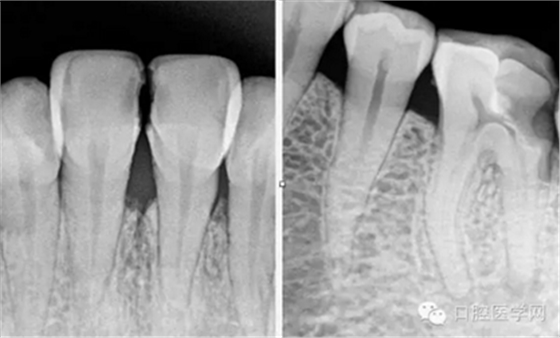

術(shù)前片(治療前知道齲壞的程度,根管的走向)

試尖(檢查是否恰填)

根充(從術(shù)后X光片可以看出根管充填完整,專業(yè)上叫恰充)